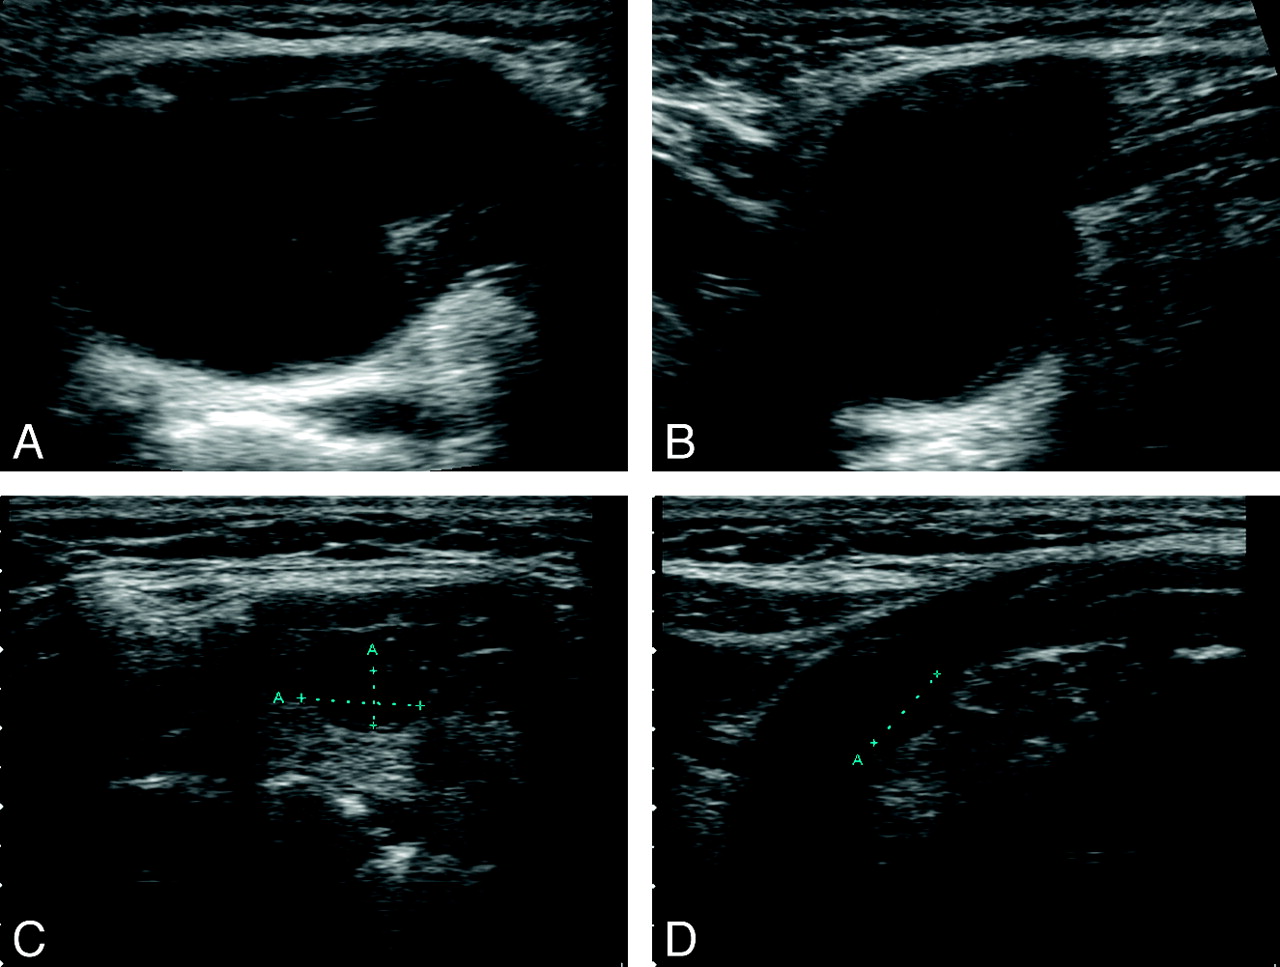

A 39-year-old woman (patient 11). Axial (A) and longitudinal (B) sonograms show a multiloculated TGDC in an infrahyoid location (1.2 × 2.0 × 2.2; volume, 2.76 mL). Sagittal CT scan (C) shows that the TGDC wraps around the hyoid bone (arrows). Axial (D) and longitudinal (E) sonograms and a sagittal CT scan (F) obtained 11 months after EA. Arrowheads indicate shrinkage of the TGDC (0.66 × 0.85 × 1.18; volume, 0.35 mL; volume reduction, 87.5%).

The mean clinical follow-up period of 11 patients was 14.4 ± 6.9 months (range, 3–29 months). The mean follow-up period of 10 patients who underwent US examinations was 13.6 ± 8.1 months (range, 3–29 months). The mean volume reductions at 0–6, 6–12, 12–29 months, and last follow-up examinations were 67.3% ± 24.6%, 62.1% ± 28.5%, 75.4 ± 24.3%, and 81.3% ± 22.3%, respectively. Technical success (volume reduction of >50% in US examination) was achieved in 8 of 10 patients (Figs 1 and 2). At last follow-up examinations, the volume of the treated TGDCs had decreased significantly from 6.0 ± 8.4 mL to 0.36 ± 0.38 mL (P = .005). Also the mean symptoms and cosmetic-grading scores had improved significantly from 4.0 ± 1.0 to 0.7 ± 1.0 (P = .005) and from 3.9 ± 0.3 to 1.5 ± 0.8 (P = .003), respectively.